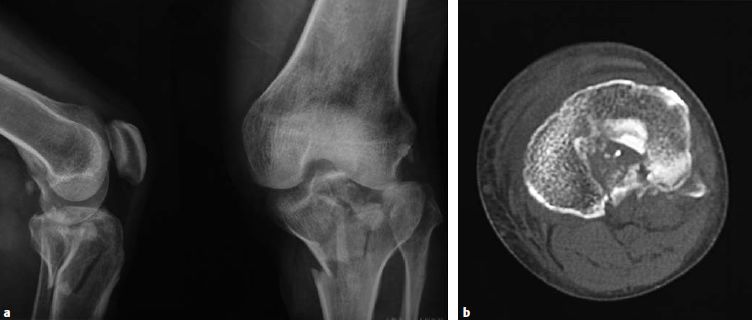

外侧柱骨折由伸膝‑外翻暴力造成,因此后续的复位和支撑固定必须防止外翻畸形的再发生。推荐采用前外侧入路。单纯劈裂型骨折(41B1.1)可以通过拉力螺钉、支撑钢板或更常用的二者之联合来进行固定。劈裂合并塌陷型(41‑B3.1)是指外侧柱骨折合并关节面塌陷,完善的术前检查(例如,CT扫描)是精确评估关节面损伤的关键(图6.8.1‑20),将塌陷的骨块复位后,克氏针临时固定有助于稳定关节面,骨折的最终固定最好使用钢板,拉力螺钉可以单独或者经钢板联合应用。

图6.8.1-20 a-d

a  CT冠状位图像显示外侧平台的劈裂-塌陷骨折;b  CT横断位显示外侧平台前外侧关节面的严重缺失;c-d  三维CT图像